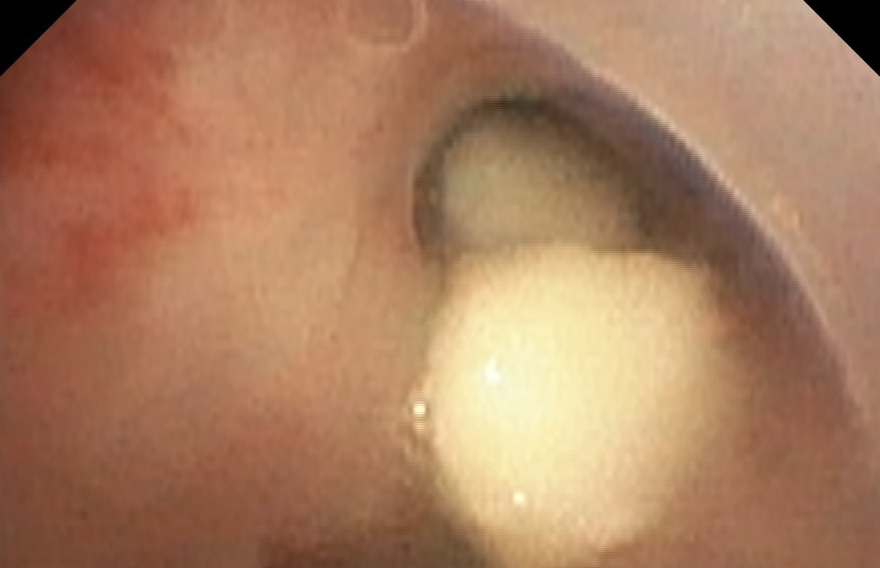

ކުޑަކުއްޖާގެ ވައިނޮޅީގައި ކެޝޫނަޓެއް ތާށިވެފައި

ދޮޅު އަހަރުގެ ކުޑަކުއްޖެއްގެ ނޭވާ ހޮޅީގައި ކެޝޫނަޓެއް ތާށިވެ ނުރައްކާ ވެއްޖެ އެވެ.

ނޭވާލާނިޒާމުގެ ބަލިތަކާ ބެހޭ އައިޖީއެމްއެޗުގެ ހާއްސަ ޑޮކްޓަރު، މުހައްމަދު އިސްމާއީލް މިއަދު ކުރެއްވި ޓްވީޓެއްގައި ވިދާޅުވީ ނޭވާހޮޅީގައި ތާށިވި އެ ބަދަންކޮޅު ނެގޭގޮތްވީ ދެ ގަޑިއިރުގެ އޮޕަރޭޝަނަކަށް ފަހު ކަމަށެވެ. ކުޑަކުއްޖާގެ ހާލު މިހާރު ރަނގަޅު ނަމަވެސް، އެ ހާލަތު ޑޮކްޓަރު ސިފަ ކުރެއްވީ ވަރަށް ނުރައްކާތެރި ކަމެއްގެ ގޮތުގަ އެވެ.

މި ފަދަ ގިނަ އޮޕަރޭޝަންތައް ކުރައްވާފައިވާ މުހައްމަދު އިސްމާއީލް ވިދާޅުވީ ބަދަންކޮޅު ނެގުމަށް ކުރި އޮޕަރޭޝަނުގެ ތެރެއިން، ބައެއް ވަގުތުގައި ޑޮކްޓަރުން ވެސް ނޭވާ ހިފަހައްޓާލަން ޖެހިވަޑައިގެންނެވި އެވެ. އެއީ ކެޝޫނަޓް އެއް ފަރާތަކަށް ވެއްޓި، މައި ދެހޮޅި ބްލޮކް ކޮށްލަން ޖެހުމުންނެވެ.